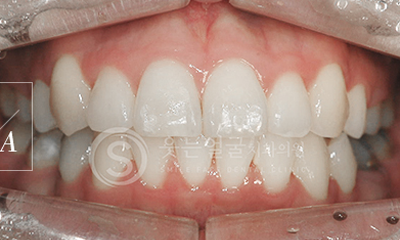

한눈에 보는

치아교정 전후사진